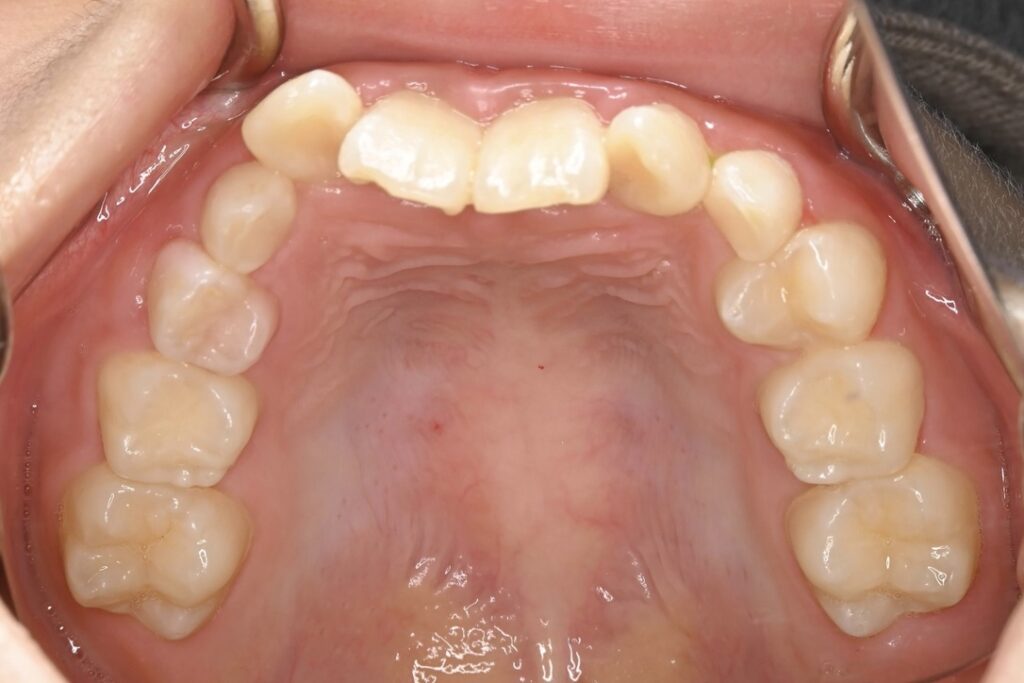

BEFORE

AFTER

主訴 通っている歯医者で矯正した方がいいと言われて気になっている。下の前歯がでこぼこしている。

診断名・主な症状 下顎前歯の叢生を伴う過蓋咬合

治療内容 上下の歯並びの幅を拡げつつ、前歯の関係を改善しました。

使用装置 急速拡大装置

リンガルアーチ

機能的矯正装置(マイオブレース)